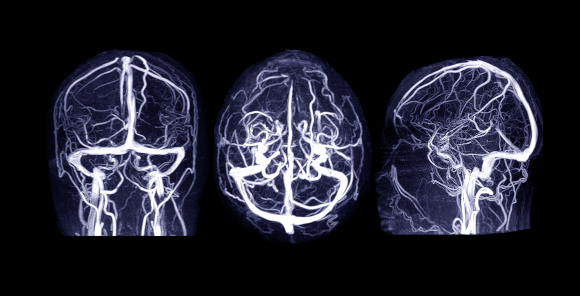

בעזרת חומרי הניגוד. תמונה ברורה של הוורידים במוח בסריקת MRI | צילום: samunella, Shutterstock